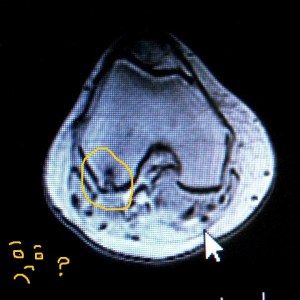

But I’ve been hobbled by a torn meniscus and been made entirely weepily furious about the American healthcare system… And that does require a rant – I have elaborated in this sister post.